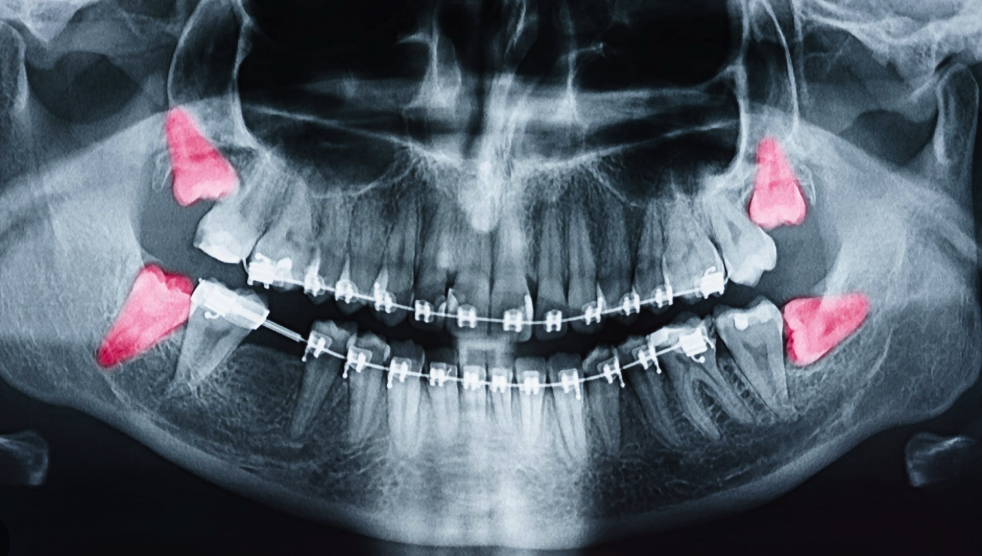

• Wisdom teeth, or third molars, are the final set of teeth to emerge, typically one in each mouth quadrant. While most people have four, variations exist, with some individuals having fewer or none at all, which can be considered fortunate.

• Not everyone requires wisdom teeth removal if their teeth align correctly. However, due to insufficient jaw space, many individuals need them removed to prevent potential damage. Improperly aligned wisdom teeth can lead to tooth, gum, and bone damage, infections, cavities, and discomfort. In rare cases, they might even cause cysts or tumors, threatening nearby nerves and structures.

Wisdom teeth, or third molars, typically emerge between the ages of 17 and 25. Many individuals experience complications due to limited space in the mouth, leading to impaction, infection, and damage to adjacent teeth. Bone grafting can play a critical role in the successful removal of wisdom teeth for several reasons: